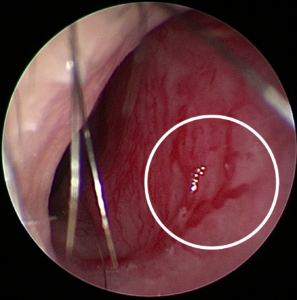

Hình 5: Bệnh nhân N.T.H 49 tuổi, vào viện vì tình trạng nhức đầu, nghẹt mũi, hơi thở hôi, chảy máu mũi Trái thường tái phát. Phát hiện sớm và nhập viện với chẩn đoán viêm xoang hàm do nấm, được chỉ định phẫu thuật nội soi lấy nấm để điều trị nguyên nhân tại Khoa Tai mũi họng Bệnh viện Quốc tế Becamex, tránh biến chứng ổ mắt, sọ não.

Hình 6: Kết quả sau phẫu thuật bệnh nhân N.T.H 49 tuổi, chảy máu cam nguyên nhân Viêm xoang do nấm Aspergillus.